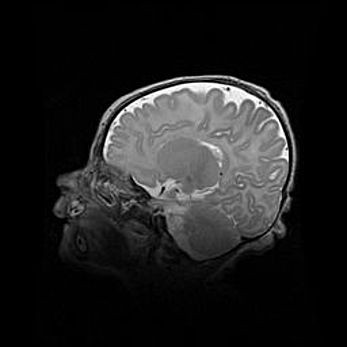

Мальформация Денди-Уокера. Киста задней черепной ямки.

Агенезия мозолистого тела.

Возраст: 2,5 месяца

Вес: 2420 г

Пол: женский

Окружность головы: 37 см

Срок гестации: 32 недели

Мальформация Денди—Уокера — редкий вид патологии ЦНС, представляющий собой врожденный порок развития каудального отдела ствола и червя мозжечка, ведущий к неполному раскрытию срединной (Мажанди) и латеральных (Лушка) апертур IV желудочка мозга. Для этогно синдрома характерна триада симптомов: гипотрофия червя мозжечка и/или полушарий мозжечка, кисты задней черепной ямки, гидроцефалия различной степени. В 70% случаев порок сочетается и с другими аномалиями головного мозга, в частности с агенезией мозолистого тела.